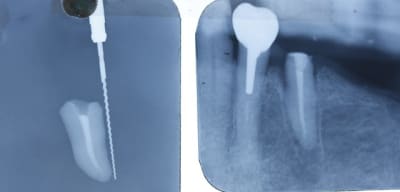

ce matin ,

il etait question d'enlever une vielle racine qui etait support de bridge supportant un ic . genre tres creuse avec les bords bien fin . où il faudrait faire une mega elongation...

et puis quand je l'ai enlevé , je l'ai trouvé bien sympatique cette racine . elle me disait pourqoi moi ? pourqoi moi ? vivre ! , vivre ! :-)))

aller , parce que ç est toi :

hop un ptit coup de lime d'endo et de spaden .

hop taille peripherique

et zou dans le trou tu iras et pas jusqu'au fond , ça t'apprendra .

mince ,j'ai oublié de cureter le fond de l'alvéole !

re mince ,les poils de compresse se sont collés , on dirait une portugaise , relavage au jus d'anesthesie ,et froti frota!

heureusement que je l'ai mise à l'envers , sinon elle serait partie direct au fond . tu vas rester là ,dis , pas bouger ,hein ?

mg 0896 xqjdum - Eugenol

Je l'ai indiqué par des flèches la lyse osseuse.

" Je l'ai indiqué par des flèches la lyse osseuse. "

où ça Chatondecarte ?

tu as oublié d'envoyer la photo ?